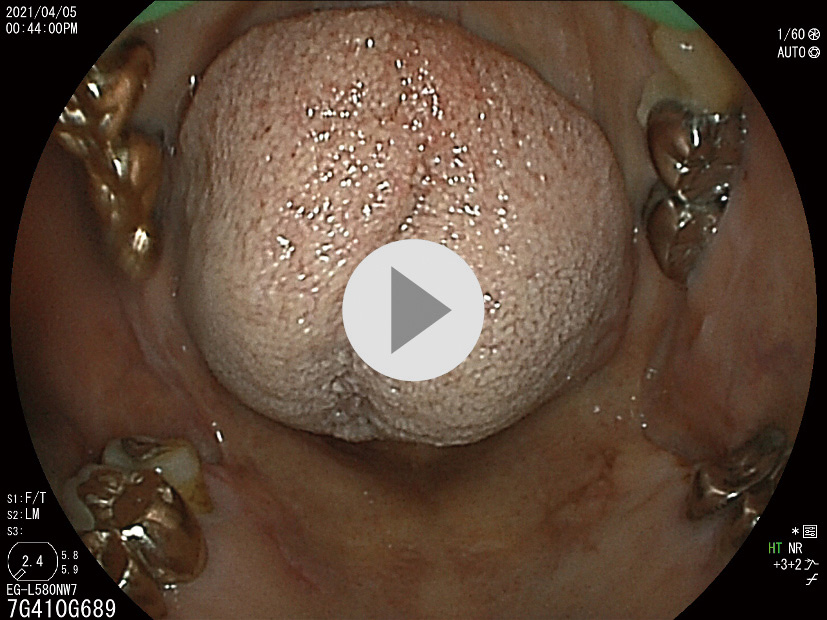

【症例3】80歳代,女性.

主訴:咽頭違和感,呑酸,げっぷ,前屈時の胸やけ (Fスケール7点)

既往歴など:強皮症 (limited type).H. pyloriの除菌歴なし.非喫煙,習慣飲酒 (赤ワイン1~2杯/日).

悪性腫瘍の家族歴:なし

内服歴:ファモチジン20 mg,サルポグレラート塩酸塩3錠/日.

内視鏡検査法:鎮痙剤・鎮静剤なし,炭酸ガス送気使用,経口挿入.IEE (BLI,LCI併用).

使用機種:EG–L580NW7 (富士フイルム,原色カラーフィルター同時方式電子内視鏡)

検査場所:獨協医科大学病院 (栃木県下都賀郡)

内視鏡画像:ⓔ動画11-1-6 (122枚の静止画を連続再生)

内視鏡検査所見・report (図3) 参照

内視鏡検査ビデオ:ⓔ動画11-1-7参照

検査時間:14分

撮影枚数:122枚

生検結果:なし